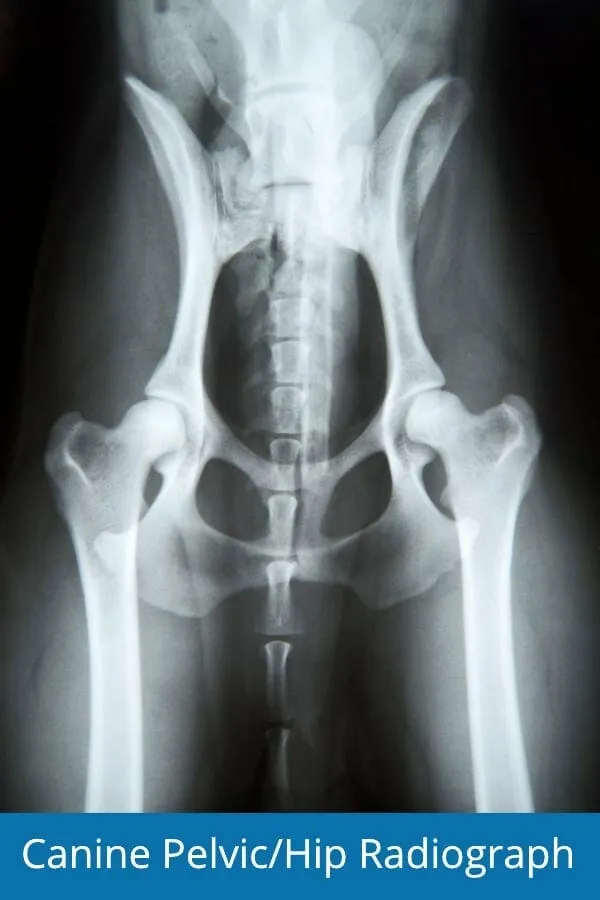

Veterinary radiograph of a dog's hip joints, demonstrating potential signs of osteoarthritis, which can also affect front leg jointsThis X-ray shows a dog’s hip joints, but similar radiographic changes can be seen in the elbows and shoulders when front leg arthritis is present.

Some common changes seen on X-rays of dogs with arthritis (whether in hips, elbows, or shoulders) include:

- Osteophytes and enthesophytes (bone spurs)

- Flattening of the joint surfaces

- Thickened joint capsules

- Subluxation (partial dislocation) of the joint